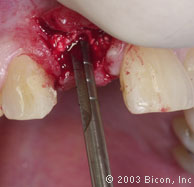

16. | 利用3.0mm的手动扩孔钻扩大成形,在脆弱的植骨区用手动钻预备,可以获得更多的控制。 |

17. | 用4.0mm的手动扩孔钻扩大成形。 |